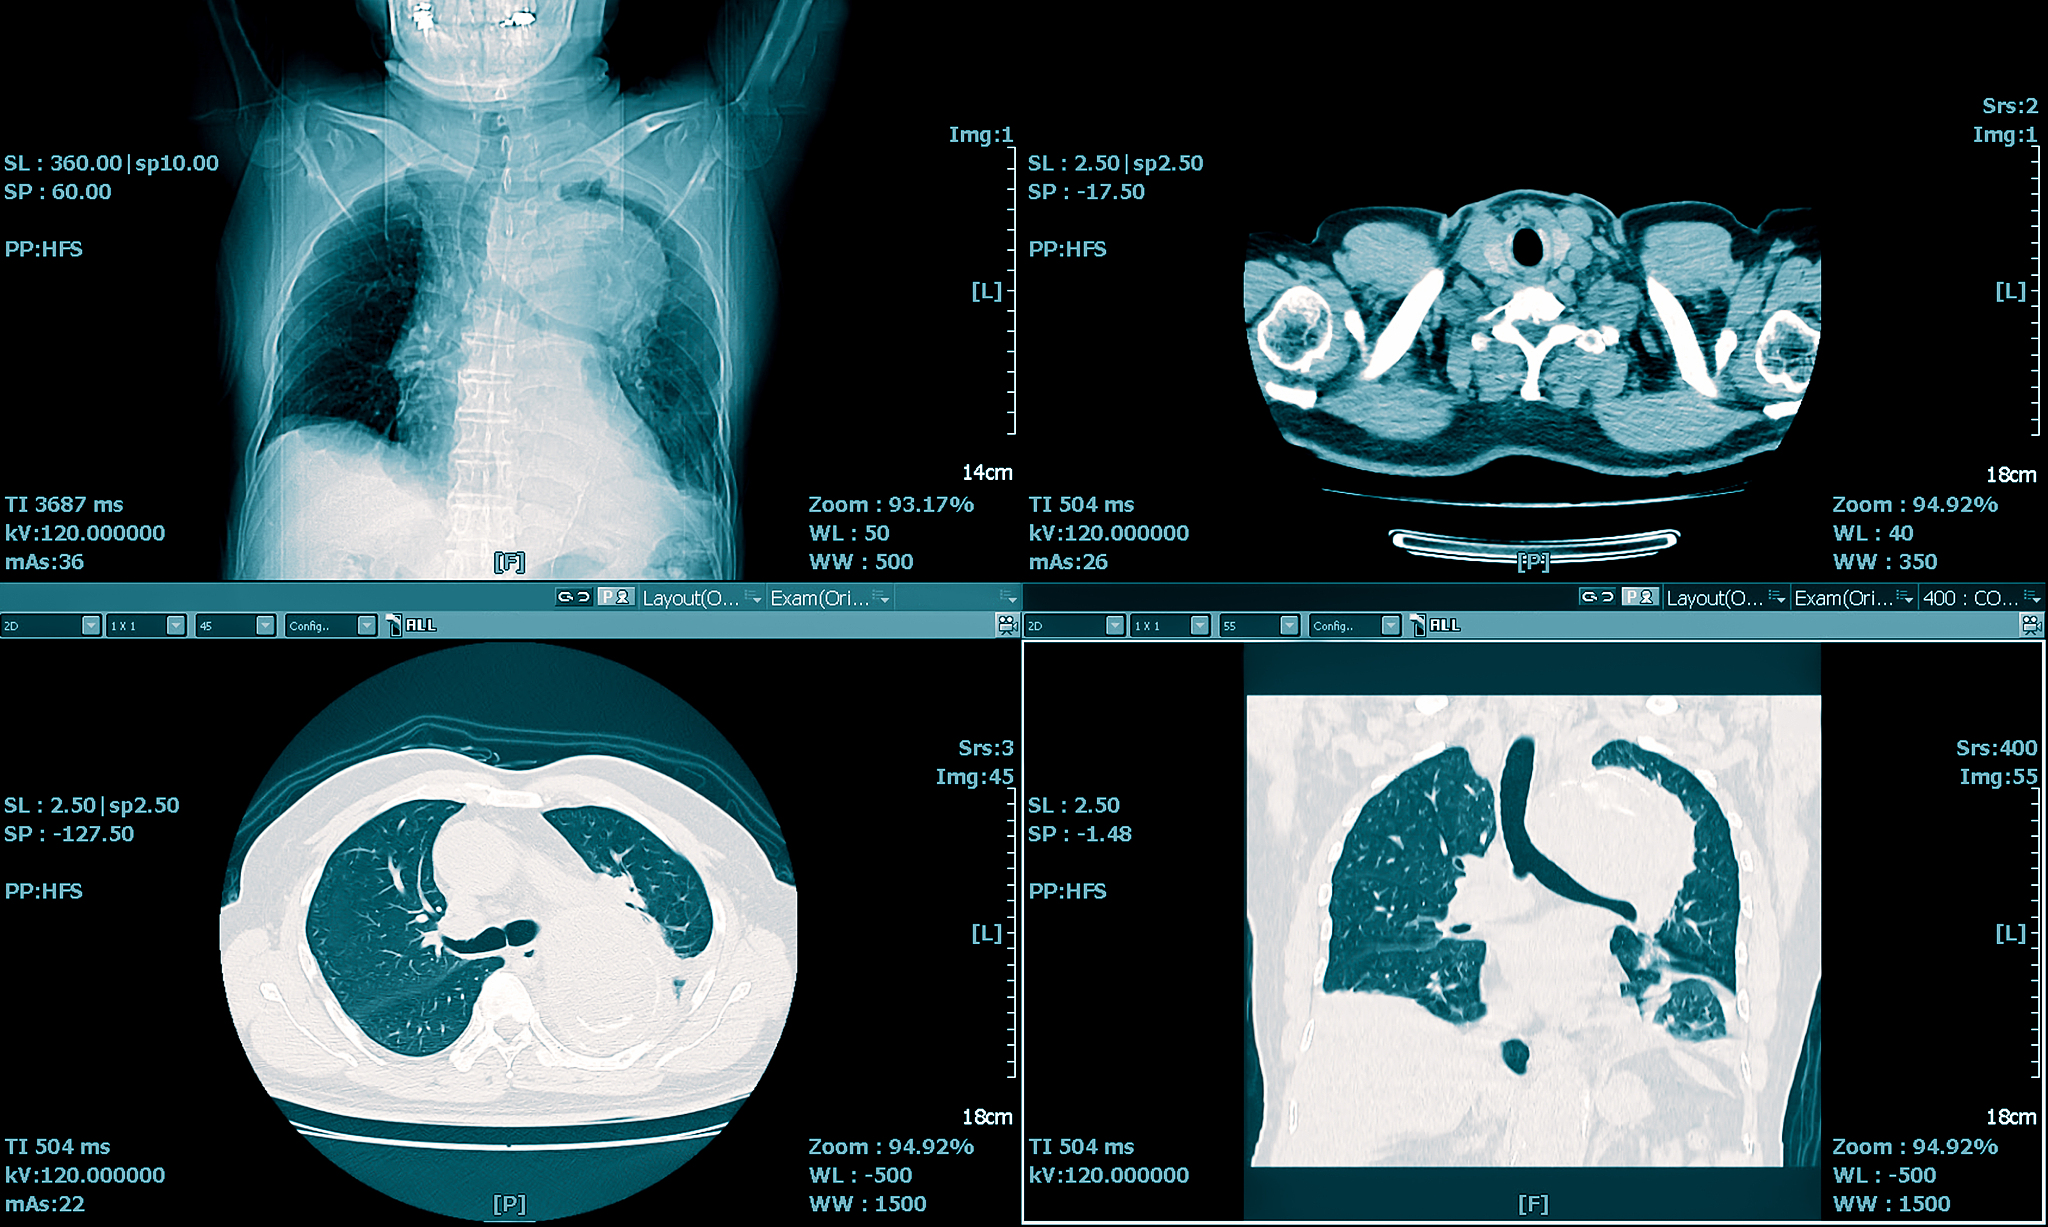

乳腺成像时一般采用较软的 X 射线。该射线透过乳腺时最可能发生以下哪种现象: a特征辐射;b连续辐射;c韧致辐射;d光电效应。

(d) 光电效应。